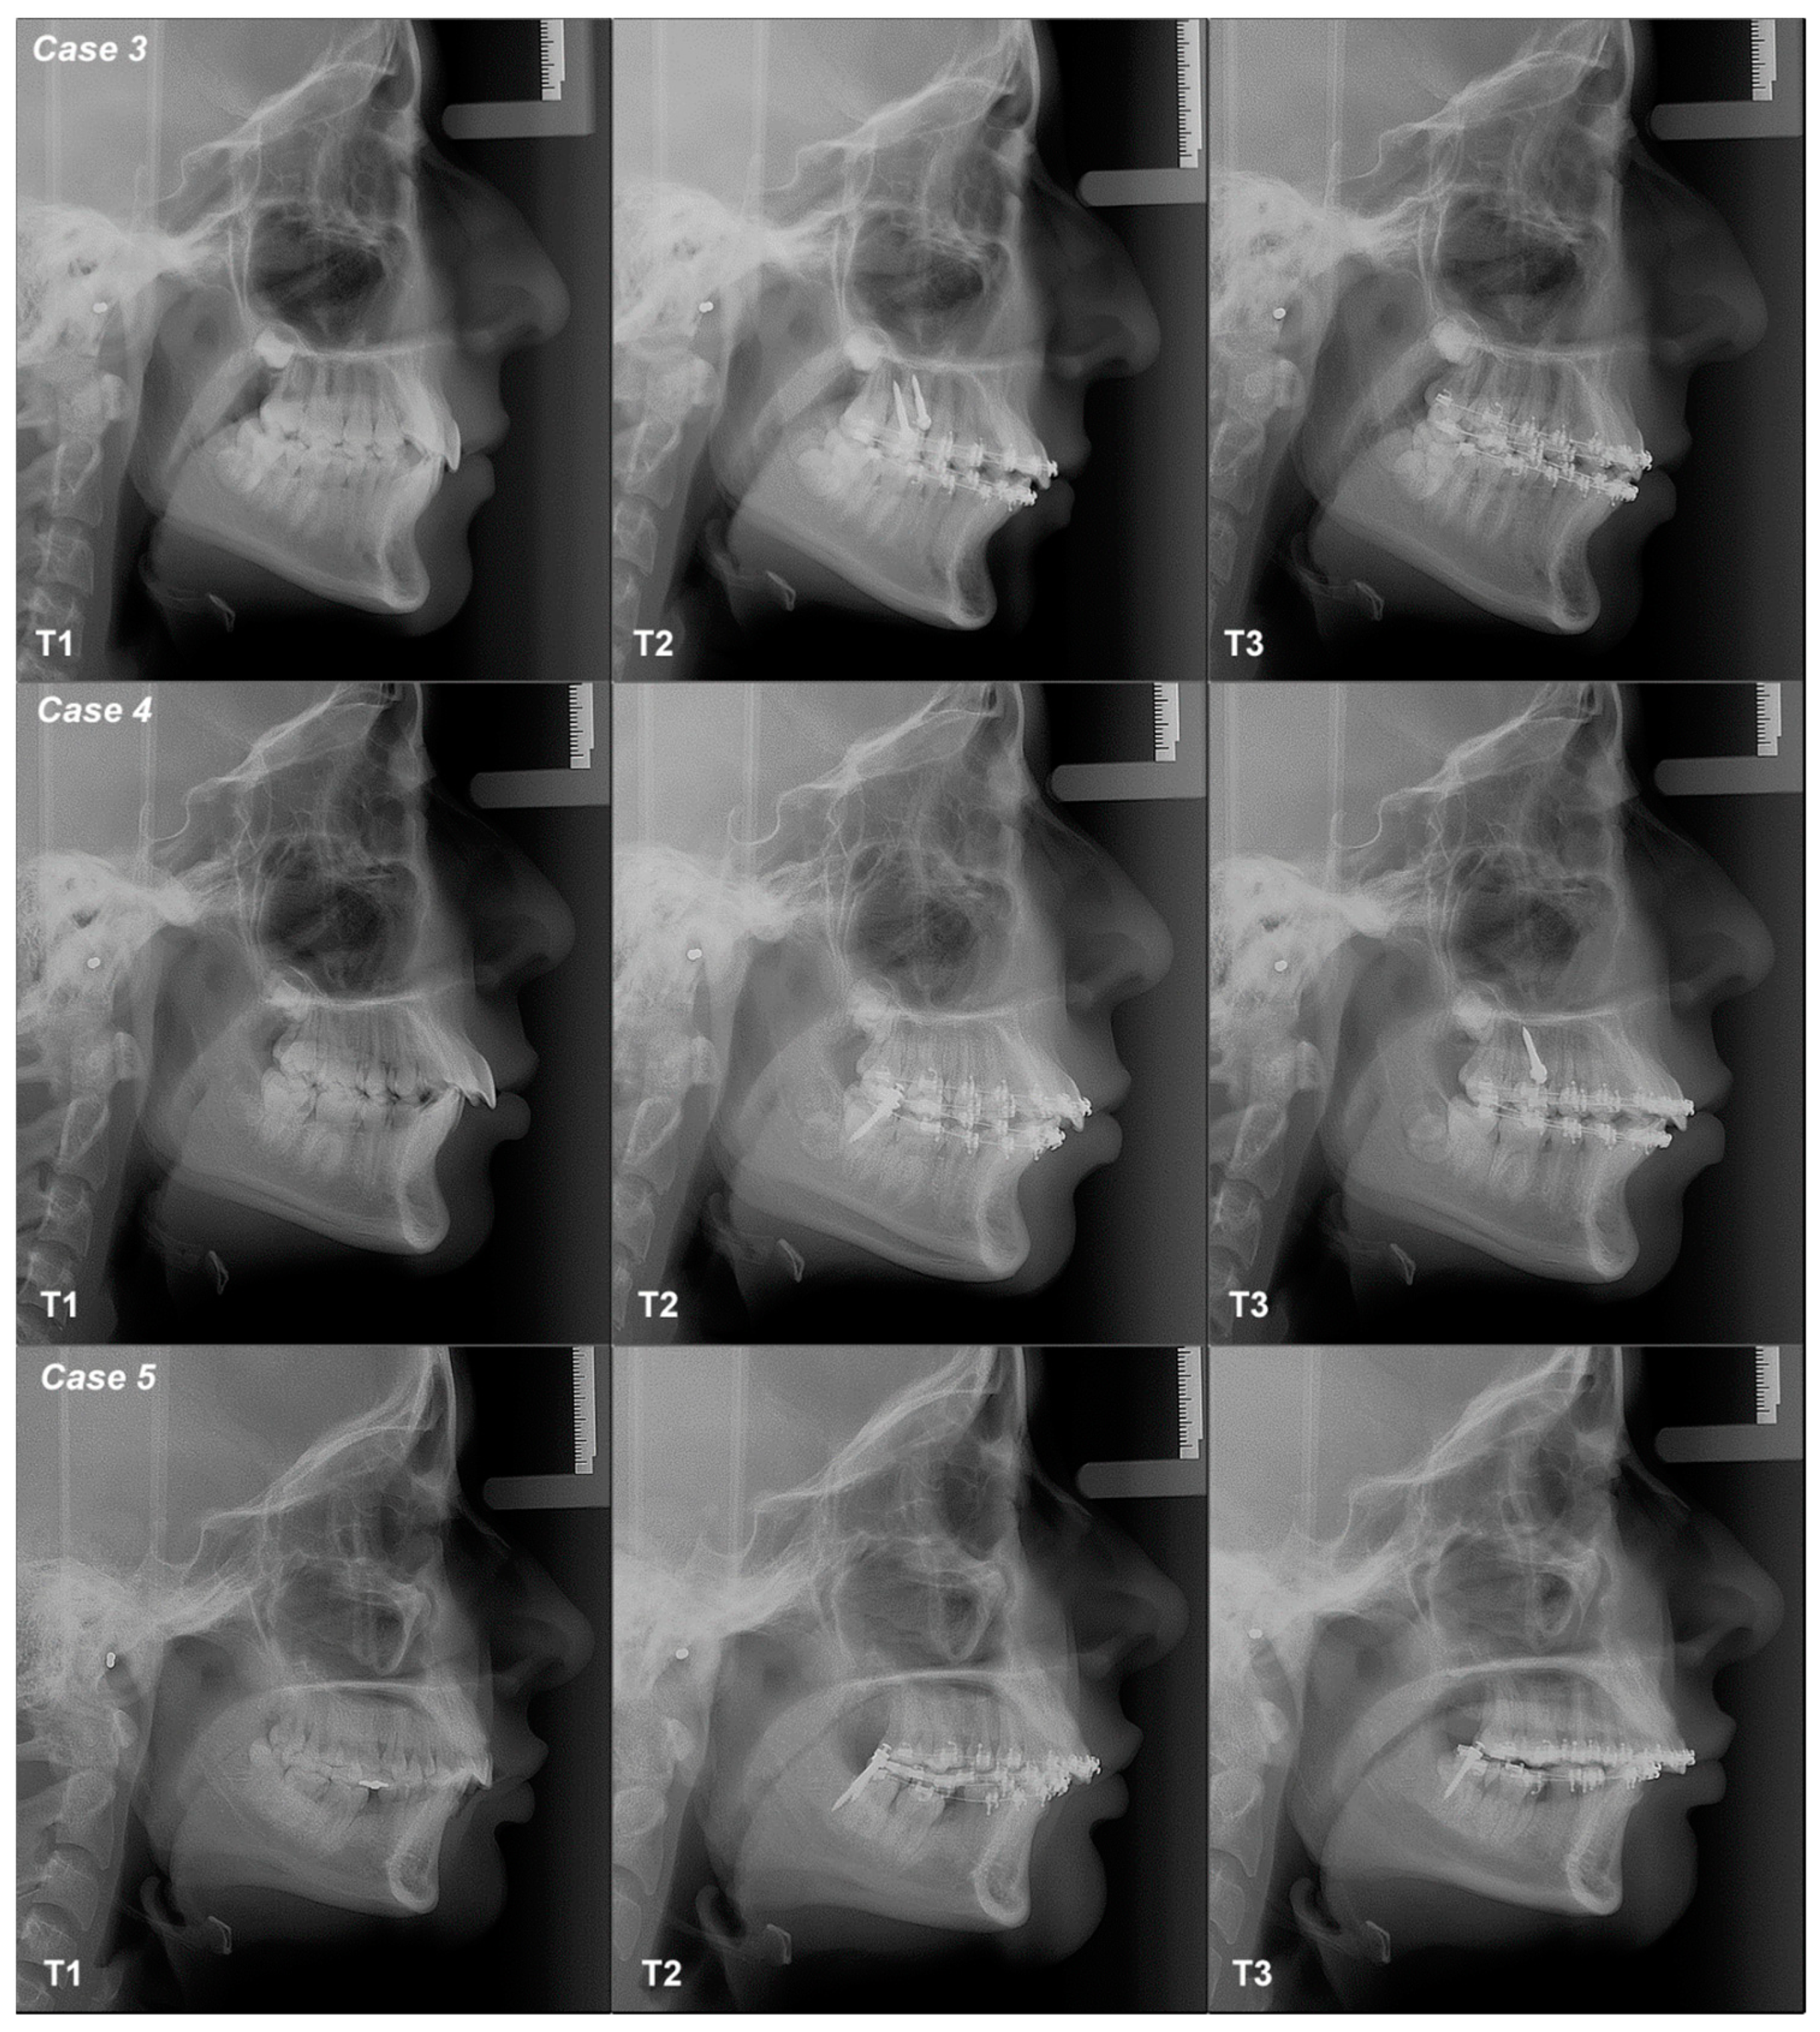

3.2.3. Case 3

3.2.4. Case 4

3.2.5. Case 5

| 3 | Class II Neutral Angle | Maxilla | T1–T2 | Flattened | Flattened | Flattened | Increased | Decreased | Increased | Not changed | Not changed |

| T2–T3 | Tipped | Tipped | Tipped | Decreased | Decreased | Decreased | Changed | Not changed | |||

| T1–T3 | Tipped | Tipped | Flattened | Decreased | Decreased | Decreased | Changed | Not changed | |||

| 4 | Class II Low Angle | Mandible | T1–T2 | Flattened | Flattened | Flattened | Increased | Increased | Increased | Not changed | Not changed |

| T2–T3 | Tipped | Tipped | Tipped | Decreased | Decreased | Decreased | Not changed | Not changed | |||

| T1–T3 | Tipped | Flattened | Flattened | Increased | Decreased | Decreased | Not changed | Not changed | |||

| 5 | Class II Low Angle | Mandible | T1–T2 | Tipped | Tipped | Flattened | Increased | Decreased | Decreased | Not changed | Not changed |

| T2–T3 | Flattened | Flattened | Tipped | Decreased | Decreased | Increased | Not changed | Not changed | |||

| T1–T3 | Tipped | Tipped | Flattened | Decreased | Decreased | Decreased | Not changed | Not changed | |||